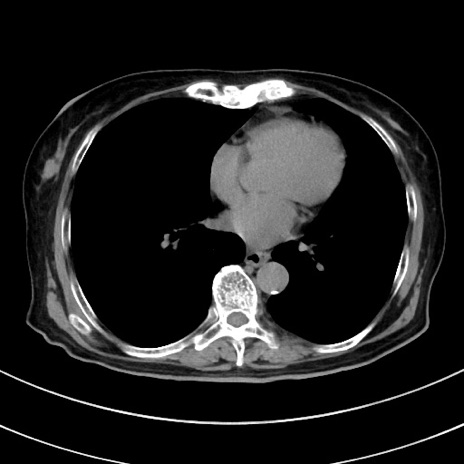

症例33(横断像)

【症例】70歳代 女性

【主訴】心窩部痛

【現病歴】延髄病変の精査・加療にて神経内科入院中。本日より心窩部痛あり。

【身体所見】右下腹部を中心に圧痛と反跳痛あり。

【データ】WBC 10900、CRP 0.02